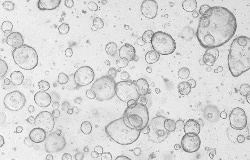

Human biliary cancer organoids

Human cholangiocarcinomas organoids were cultured with FGF2 (Cat#: 10014-HNAE), HGF (Cat#: 10463-HNAS), FGF7 (Cat#: 10210-H07E), EGF (Cat#: 50482-MNCH), FGF10 (Cat#: 10573-HNAE), NOG (Cat#: 50688-M02H), and RSPO1 (Cat#: 11083-HNAS). Image Credit: Sino Biological US Inc.